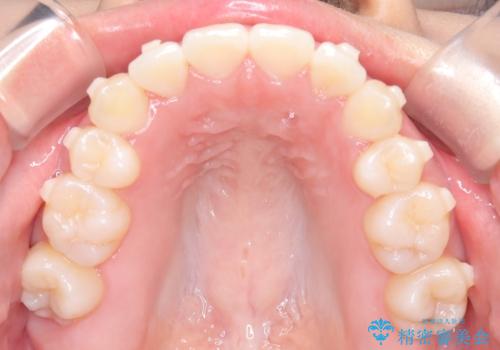

- 前歯のでこぼこが気になると来院されました。

マウスピース矯正治療を選択しました。

奥歯の噛み合わせは綺麗に噛んでいたため、前歯の叢生(でこぼこ)を、短期間で治療完了するように計画しました。